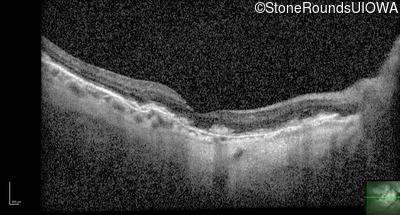

Optical Coherence Tomography - Right - 20/25 +1

Exemplar / OCT Stack

OCT Stack